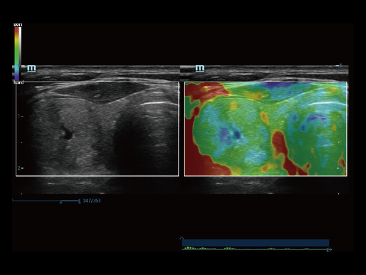

Desde que se fund├│ la compa?├Ła, Mindray ha explorado incansablemente nuevas formas de mejorar la confiabilidad del diagn├│stico. Con la revolucionaria tecnolog├Ła de ZONE Sonography?, la nueva plataforma ZST+ de Resona?7 lleva la calidad de la imagen por ecograf├Ła a un nivel superior mediante el procesamiento de datos de canal y la adquisici├│n de zona.

Adem├Īs de la calidad de imagen de primer nivel, Resona?7 tambi├®n mejora las capacidades de investigaci├│n cl├Łnica con el revolucionario V?Flow para la evaluaci├│n hemodin├Īmica vascular y con la adquisici├│n de planos m├Īs inteligente a partir de conjuntos de datos 3D para el diagn├│stico del SNC fetal. Al combinar el funcionamiento multit├Īctil basado en gestos m├Īs intuitivo y todas las caracter├Łsticas cl├Łnicas esenciales, Resona?7 realmente lidera las novedades en innovaci├│n de ecograf├Łas.